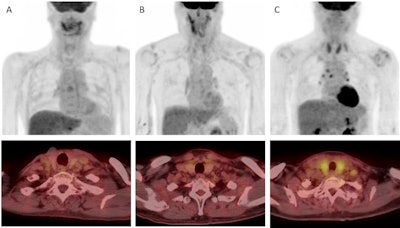

Examples of thyroid visual grade in the study cohort (upper: maximum intensity projection, lower: transaxial view). A) In grade 1, thyroid uptake is less than blood pool uptake. B) In grade 2, thyroid uptake is equal to or higher than blood pool uptake, but less than liver uptake. C) In grade 3, thyroid uptake is equal to or higher than liver uptake. Image courtesy of Cancer Imaging.Next, a quantitative analysis of thyroid functioning volume revealed that F-18 FDG radiotracer uptake was significantly lower in patients who developed hypothyroidism than in those who did not (10.61 cm3 versus 16.30 cm3, p < 0.001).